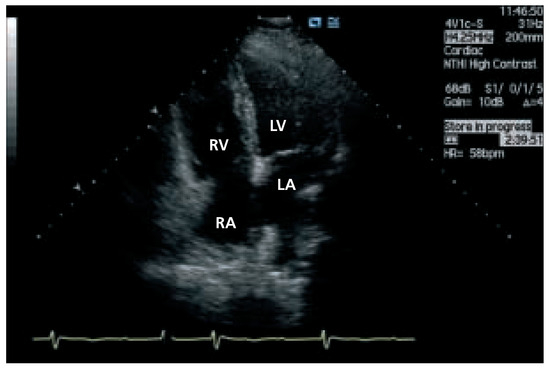

Case description A 70-year-old former athlete complained about a twenty-year history of paroxysmal atrial fibrillation with onset at rest and during the night, which became persistent in the last three years [...]